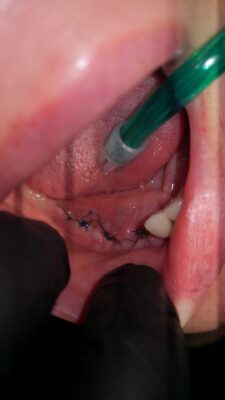

Hey guys! Question… how would you treat an early implant dehiscence? I ve tried placing them with gbr and membrane but i got dehiscence after 3 weeks (patient already left the country- I wasn t informed about that she wanted to leave). Where the incision line was, i can see my cover screws. I know that i shouldve grafted first with ctg to…